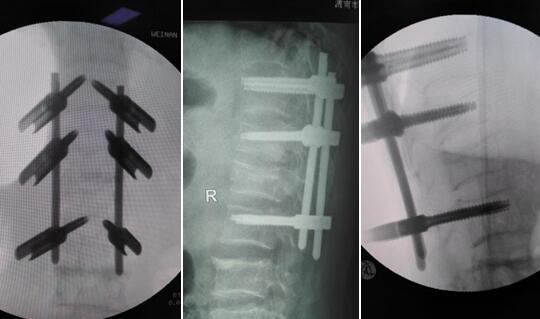

近日,我院骨二科对一例多发胸腰椎骨折的患者采用经皮穿刺微创椎弓根钉棒固定技术治疗,椎弓根螺钉在透视下导针置入,伤口仅有六个1.5cm的小伤口。术后第2天即下床活动,患者对手术效果非常满意。

术中及术后X线片

术中C臂下进行操作